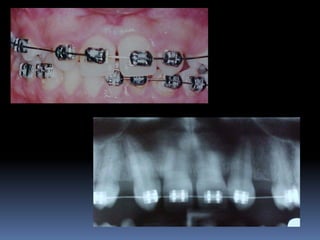

•Necessidades de reabilitações prévias

Dentística, periodontia, cirurgia, prótese, endodontia , ortodontia e DTMs

•Áreas de interesse implantar

Perdas dentárias , tecido ósseo e tecido mucoso